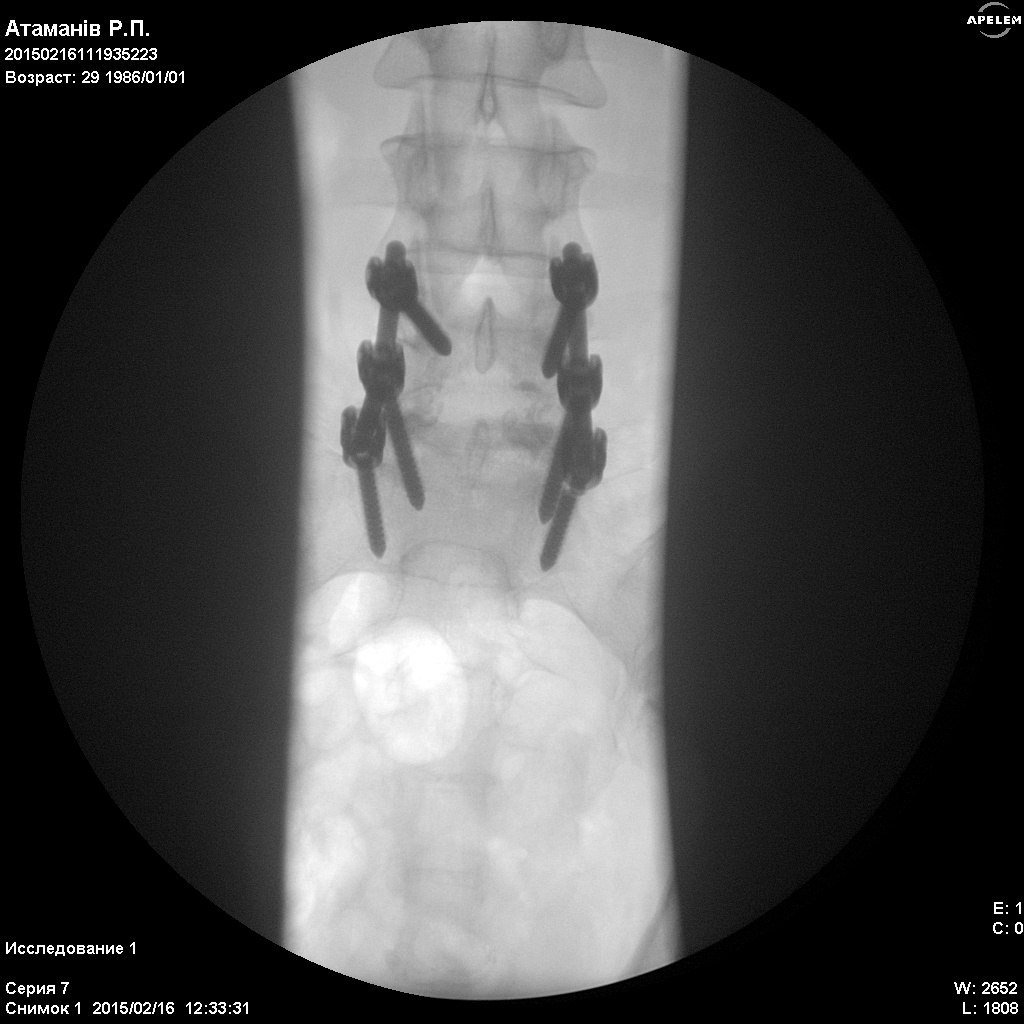

У Харківському державному інституті патології хребта і суглобів ім. проф. М.І. Сітенка, Сергію зробили операцію відкритого вправлення Л5 хребця. Та провели стабілізацію на рівні Л4,Л5-С1, конструкцією "медтронік". Тобто йому зафіксували хребет за допомогою металевих з'єднань.